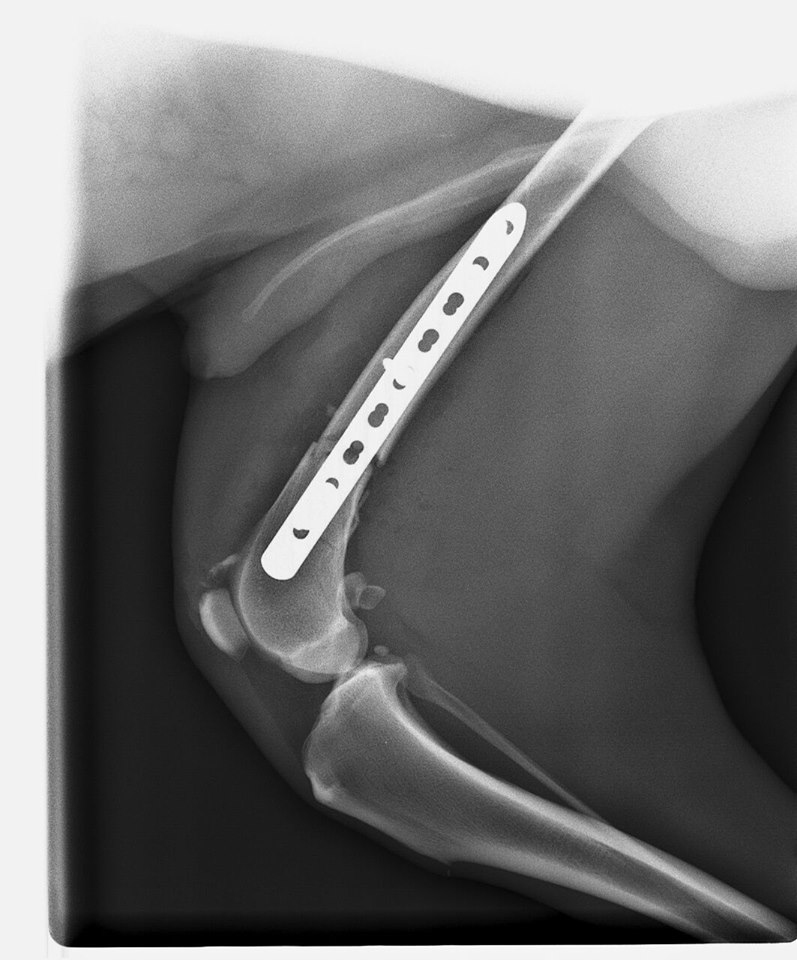

Estado de Tako tras su operación.

Tako fue operado con gran éxito de la fractura de su patita trasera. Le han puesto una placa para unir el hueso roto y evoluciona muy bien.